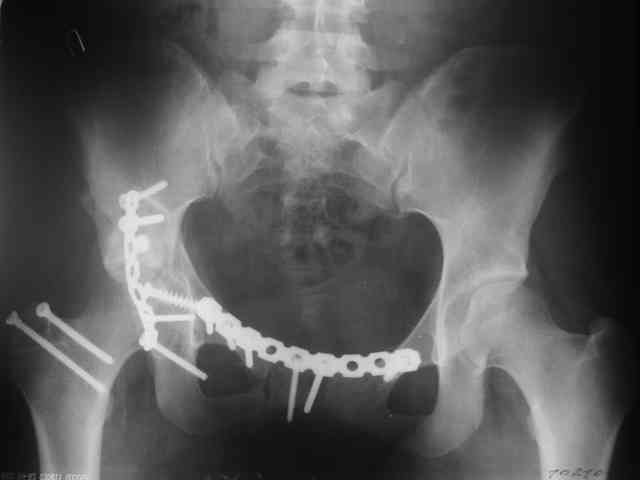

Трудности возникли сразу после рассечения большой ягодичной мыцы - короткие наружные ротаторы едва ли определялись - головка и шейка (как видно на

снимке) ушли в таз, пришлось воспользоваться дистрактором( ручные попытки выдернуть голову из под проксимального фрагмента - безуспешны) Шарнирный дистрактор - великое изобретение, без него репозиция была просто невозможна.

Дальше как обычно: рекон пластнина на заднюю колонну. Устранить смещение передней колонны из заднего доступа оказалось невозможным, пришлось

перевернуть больную на спину и из подвздошного доступа вернуть переднюю колонну на место. Другая проблема возникла с фиксацией лонной кости,

пришлось открывать ся над лобком и ретроградно двумя винтами фиксировать обе ветви лобковой кости справа и слева.

Пока всё ОК снимки сделали сегодня, но пока не сфотографировал В целом суставная поверхность конгруэнтна , по колоннам тоже вроде все ОК.

Интраопер под ЭОПом контролировал направление лонного винта - была абсолютная уверенность в правидльности направл, на постоп. снимке винт вылез :-((.

P.S. в приложении R пациентки с похожей проблемой доступа.. за исключением того, что перелом

двухколонный. Вертлугу лечили Y доступом.